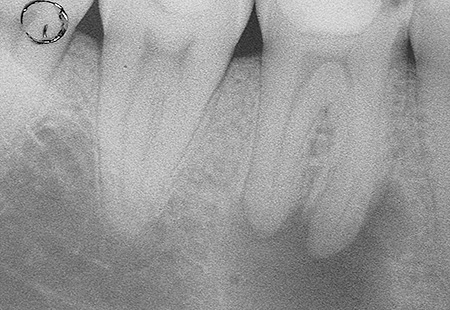

La prima fase della terapia è la corretta esecuzione di una radiografia diagnostica/preoperatoria al fine di ottenere tutte le informazioni sull’anatomia del dente in esame, successivamente si deve isolare il dente con la diga di gomma; è questo un presidio indispensabile per l’esecuzione di una corretta terapia il cui obiettivo è quello di disinfettare e detergere un sistema canalare (endodonto), e dunque il primo passo da fare è quello di evitare di contaminarlo ulteriormente con i batteri di cui la saliva è ricca. Il dente isolato con la diga di gomma è infatti completamente separato dal resto della bocca, garantendo un’ottimale detersione chimica da un lato e preservando il paziente dalla involontaria ingestione di disinfettanti o strumentario.

I batteri all’interno dei canali proliferandosi, possono dunque dar luogo ad un processo infiammatorio all’apice della radice che si può manifestare nei quadri clinici enunciati e apparire radiograficamente come una zona di radiotrasperenza dell’osso periapicale.

E’ molto importante monitorare nel tempo il ritrattamento, eseguendo radiografie di controllo a distanza che documenteranno le modificazioni morfologiche della lesione periapicale e consentiranno al clinico di pronunciarsi in merito alla guarigione e alla prognosi del singolo caso.